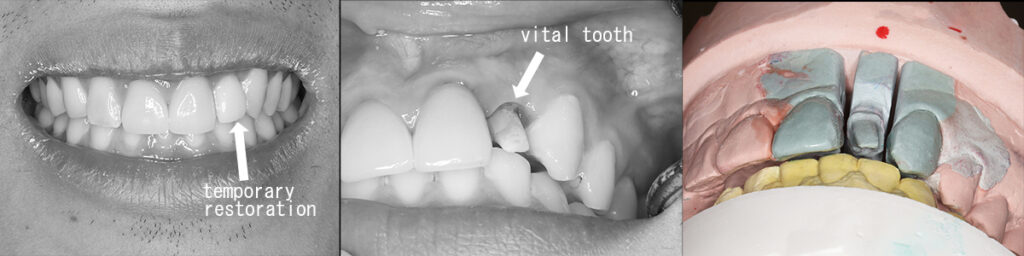

CTを見るまでもなく歯冠が前方移動できる歯間スペースがなく、修復処置が前提であるため根面を隣在歯間を通過させた後に暫間クラウン(provisional restoration)で下顎前歯の前方に被蓋させ位置関係を固定し、通法の修復治療をおこなう。

治療直後の上下前歯の被蓋関係と術前の状態

模型により術前記録と全体像を把握